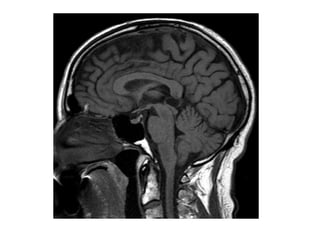

Sagittal View

1Posterior

commissure

2Cerebral aqueduct

(of Sylvius)

3 Tectum

4Fourth ventricle

5-Cerebellum

6Quadrigeminal

cistern

7 Pineal gland

8Splenium , corpus

callosum

9 Third ventricle

Sagittal View 1Posterior commissure 2Cerebral aqueduct (ofSylvius) 3 Tectum 4Fourth ventricle 5-Cerebellum 6Quadrigeminal cistern 7 Pineal gland 8Splenium , corpus callosum 9 Third ventricle